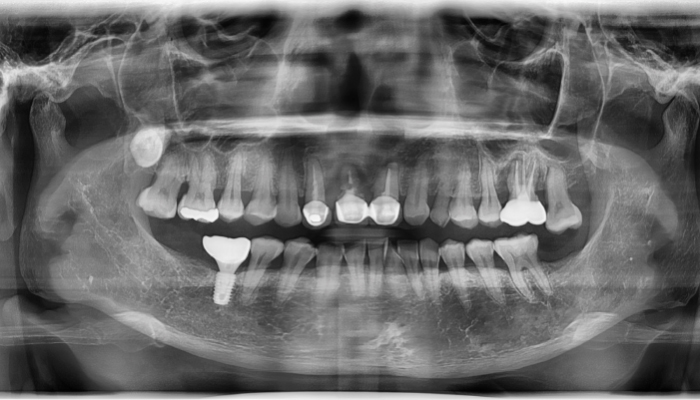

상악동거상술 전후 사례

• 식립전

식립후